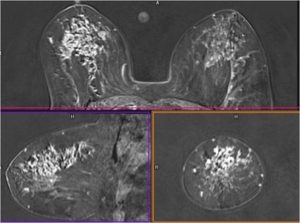

Ductal carcinoma in situ (DCIS) is a noninvasive malignancy and a nonobligate precursor to invasive cancer . Although the detection of DCIS has increased with the advent of widespread mammography screening, it is essential to have more accurate assessment of the extent of DCIS for successful breast conservation surgery. (1) DCIS most commonly appears as microcalcifications at mammography which may be amorphous, coarse, heterogeneous, or fine pleomorphic with a clustered, linear, or segmental distribution. Majority of the time, microcalcifications are the sole finding of DCIS, although focal asymmetry, diffuse increased reticular densities, focal architectural distortion or masses are also observed. (2) Mammographic determination of the extent of DCIS usually depends on the presence of calcifications. Because calcifications are not present in all cases of DCIS, such lesions are mammographically occult, contributing to a mammographic sensitivity of 70–80% . Similarly, because all involved areas may not calcify equally, the extent of disease is often underestimated on mammography. (3) Therefore, it is possible that mammography would fail to depict prognostically relevant DCIS in a large number of women in case of non calcified DCIS. Contrast-enhanced MRI of the breast is complementary to mammography in the detection of DCIS because enhancement may be seen in areas of calcified as well as noncalcified DCIS. Therefore, MRI is helpful in detection of noncalcified disease and more accurate assessment of the disease extent, improving treatment and prognosis. (4) DCIS most commonly manifests as non mass enhancement in segmental or linear/ ductal distribution with internal enhancement patterns like clumped, heterogeneous and clustered ring enhancement. In case with negative mammogram which may harbor DCIS but demonstrated by MRI, it remains important to be aware that high grade DCIS may present as a non‐calcified mammographic abnormality. High‐grade DCIS appears to be more easily detected than low‐grade, suggesting MRI may have a significant benefit in excluding high‐grade disease with a negative mammogram.

Bilateral Mammograms revealed increased reticular densities in the upper half of the right breast. A 16 mm well defined nodule seen in the left subareolar region. BIRADS 3/4 Bilateral breast ultrasound revealed extensively dilated ducts showing thickened walls and intra ductal contents corresponding to the increased reticular densities on the mammogram of right breast. Left breast revealed a 17 x 10 mm well defined low echogenic lesion with posterior enhancement in the left subareolar region. BIRADS 3 MRI showed segmental clumped / clustered ring enhancement extending from 10 to 2 O’ clock position in the right breast with extensive ductal branching and intraluminal contents extending till the nipple suspicious for DCIS. Left breast revealed a benign 16 x 14mm well defined nodule in the lower inner quadrant close to the nipple. BI-RADS-4.